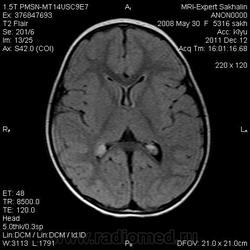

Девочка 3 года.В анамнезе -родовая травма-внутрижелудочковые кровоизлияния 1-2 ст.Задержка психического развития.Со слов мамы, "бывают истерики, хватается ручками за голову, особенно затылочную часть".Как интерпретировать изменения в желудочках, в задних рогах?Ликворную кисту ЗЧЯ отметила.

А вот гипоинтенсивное по Т2 в заднем роге левого бокового желудочка?В других последовательностях нет.

справа киста сосудистого сплетния -она же ксанутрогранулема,пртекаетбессимптомно.в эру доКТ и МРТ диагнстировались только на аутопсии,влевомсплетении -фокус пониженного МРС -возможно обезыствление или гемосидерин  ( ведь было кровоизлияние?)